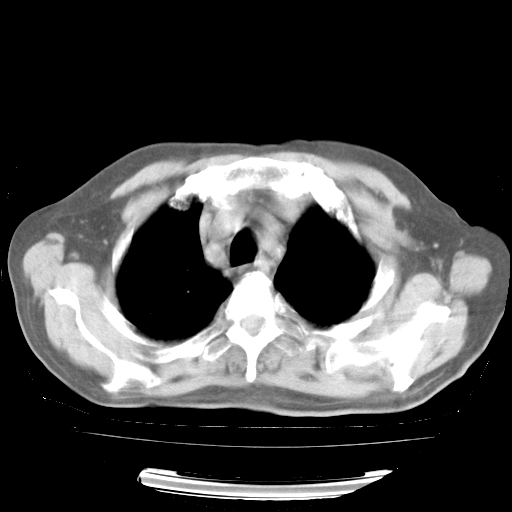

4月28日肺部CT——再次出现类似去年5月9日——透光度降低,“间质性”改变。

4月28日肺部CT——再次出现类似去年5月9日——磨玻璃样、间有“粟粒样”改变。

4月28日肺部CT